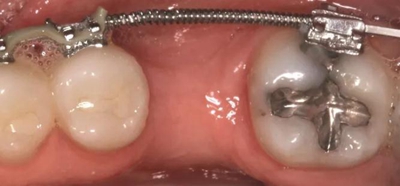

圖5g. 3 個月后完成了位點加速改建,近遠中向的修復空間和頰舌向的骨增量均增加

術(shù)后3個月,右側(cè)第一磨牙的空間約為9mm(3個月中增加了1.6mm),逐漸接近了對側(cè)第一磨牙的空間(也約9mm)(圖6a)。術(shù)后7個月的錐束CT顯示,右側(cè)第一磨牙區(qū)域獲得了2.5mm的水平骨增量(圖6b 和c)。左側(cè)第一磨牙的無牙區(qū)保持相同的尺寸,在種植體植入前也需要骨增量。

經(jīng)過最初1年的正畸排齊后,右側(cè)下頜第一磨牙無牙區(qū)的近遠中距離由6mm增至7mm,左側(cè)下頜第一磨牙的近遠中距離由7mm增至8mm(圖4)。取得患者知情同意后,采用與病例1中描述的相同技術(shù)和材料進行同期牙槽嵴增量和加速磨牙直立程序(圖5a-5g)。除了右側(cè)磨牙后區(qū),在右側(cè)第二和第三磨牙根部之間也進行了去皮質(zhì)術(shù)(圖5d)。骨增量術(shù)后,即刻將0.016×0.022 英寸帶有30° 后傾彎的鈦鉬合金絲(Dentsply)置于兩側(cè)。6周后,以半個托槽的距離進行主弓絲套推簧雙側(cè)輕加力(圖5h)。